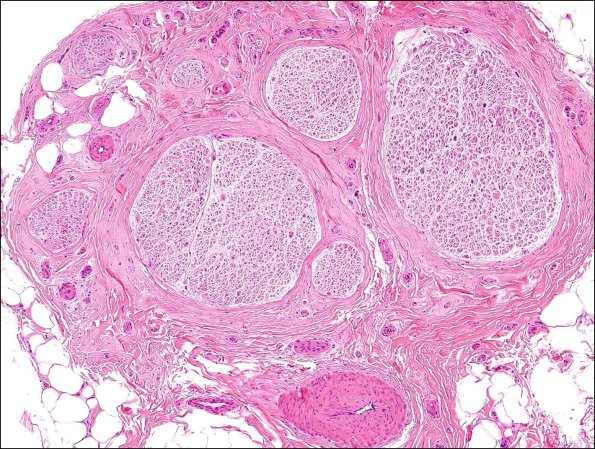

4A Nl sural H&E (Case 4) 2

Notice the marked difference in the size of the individual fascicles. (H&E)